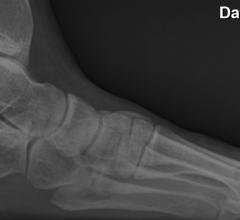

Patients suffering from chronic plantar fasciitis now have a new weapon against this debilitating foot ailment, according to research presented at the Society of Interventional Radiology's Annual Scientific Meeting.